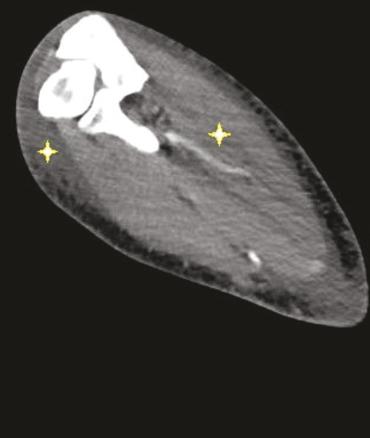

Adressé par le laboratoire aux urgences, un angioscanner thoracique et du membre supérieur droit est réalisé. Il montre un œdème prédominant au niveau des loges musculaires de l’avant-bras, et des parties molles sous-cutanées en profondeur, adjacent aux fascias musculaires (fig. 2 ). L’ensemble est évocateur d’un syndrome DOMS (delayed onset muscle soreness).

Adressé par le laboratoire aux urgences, un angioscanner thoracique et du membre supérieur droit est réalisé. Il montre un œdème prédominant au niveau des loges musculaires de l’avant-bras, et des parties molles sous-cutanées en profondeur, adjacent aux fascias musculaires (